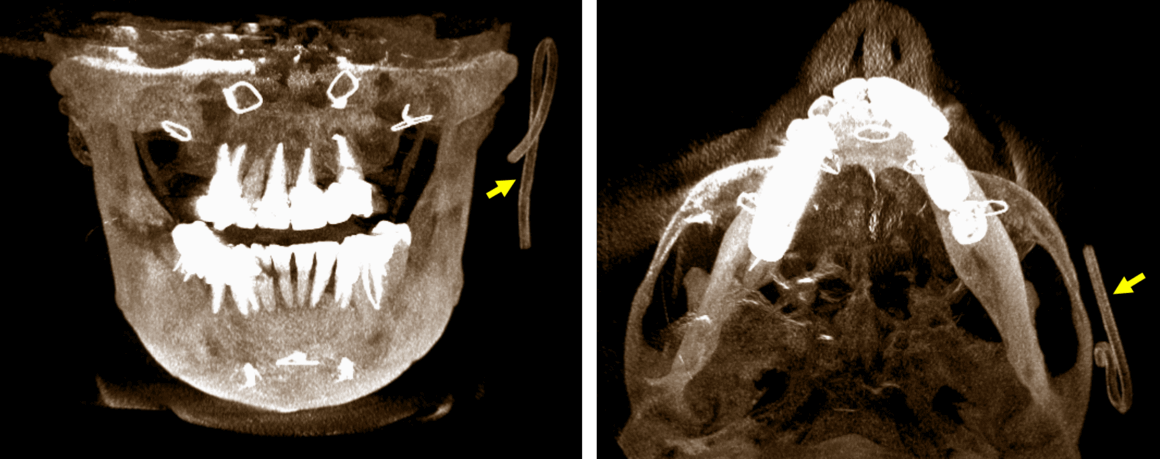

Fig.1

En la evaluación con tomografía computarizada cone beam se observa en cortes axiales (Fig.1) la presencia de un dispositivo de bordes hiperdensos y de forma tubular (flechas rojas) localizado en el lado izquierdo a nivel de la región cigomática y con el tejido blando superficial. Nótese el ocupamiento del seno maxilar derecho en relación con el aumento de la densidad ósea de sus paredes.